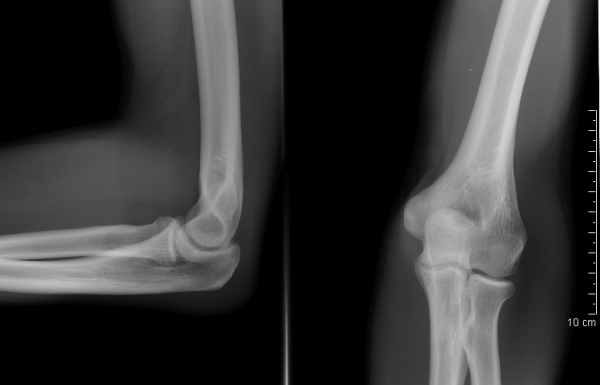

Здоровые локтевые суставы в передне-задней и боковой проекции

- Рентгенография.

- Данные анамнеза по возможности должны коррелировать с результатами рентгенографии.

Для определения перелома выполняется рентгенография локтевого сустава в двух проекциях. Этого исследования достаточно в большинстве случаев. Для более детального исследования характера перелома выполняют компьютерную томографию (КТ). С её помощью можно определить насколько разрушен отросток и определиться с тактикой лечения. Выполнять ли операцию и с использованием какой металлоконструкции. Все эти ньюансы очень важны для лучшей фиксации и наилучшего исхода лечения.

Всем пациентам следует выполнять рентгенографию в переднезадней и боковой проекциях. Также могут быть выполнены КТ или МРТ, поскольку до 30% случаев наличия свободных тел не удаётся распознать по рентгенограммам. Наиболее частым местом расположения свободных тел являются венечная и локтевая ямки и задний отдел латерального кармана.

Рентгенография локтевого сустава позволяет обнаружить воспаления, опухоли, различные изменения суставной щели и прилегающих тканях, исследовать смежные области локтевого сустава, определить характер повреждения.